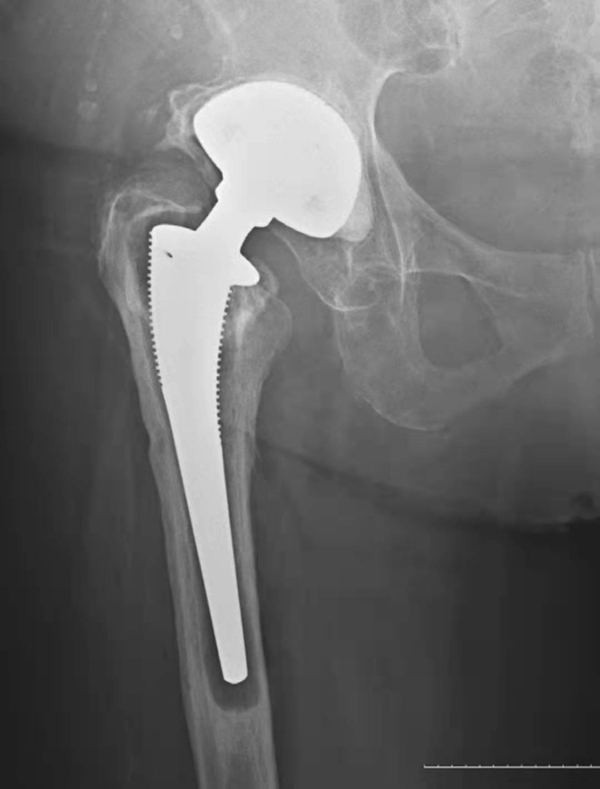

一、无菌性松动

大多数松动发生在假体柄和骨水泥之间间隙,偶然发生在髋臼帽与骨水泥之间。无菌性松动的诊断,应包括临床松动和X线松动。临床松动诊断主要根据大腿和髋部疼痛等症状。X线松动主要有以下征象:①假体周围透亮带超过2mm,且有持续增宽趋势。②假体移位下沉或旋转等超过4mm(图2,图3);③关节造影同时行牵引见造影剂向假体与骨界面渗入,仅据其中一项即可诊断。

图3 无菌性松动

平片,示右侧髋臼杯周围骨质吸收,髋臼杯松动并向上内侧移位